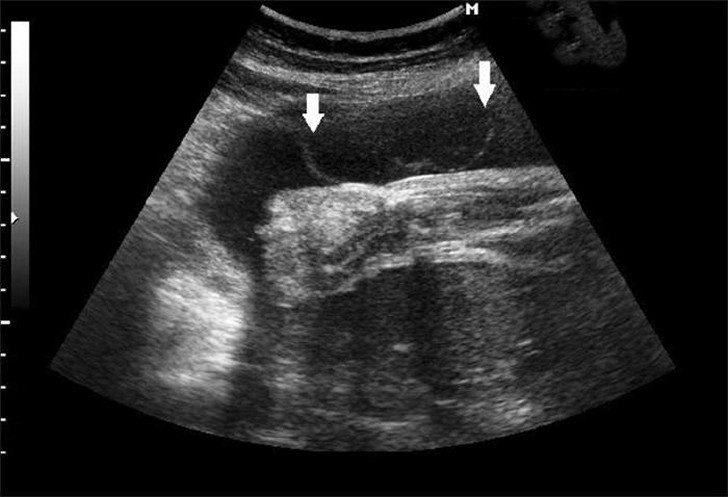

Взвесь в околоплодных водах при беременности: причины, диагностика и лечение

Во время беременности будущая мама сдает множество анализов. Часто они выявляют взвесь в околоплодных водах. Насколько она опасна и как от нее избавиться?Содержание статьи Что...